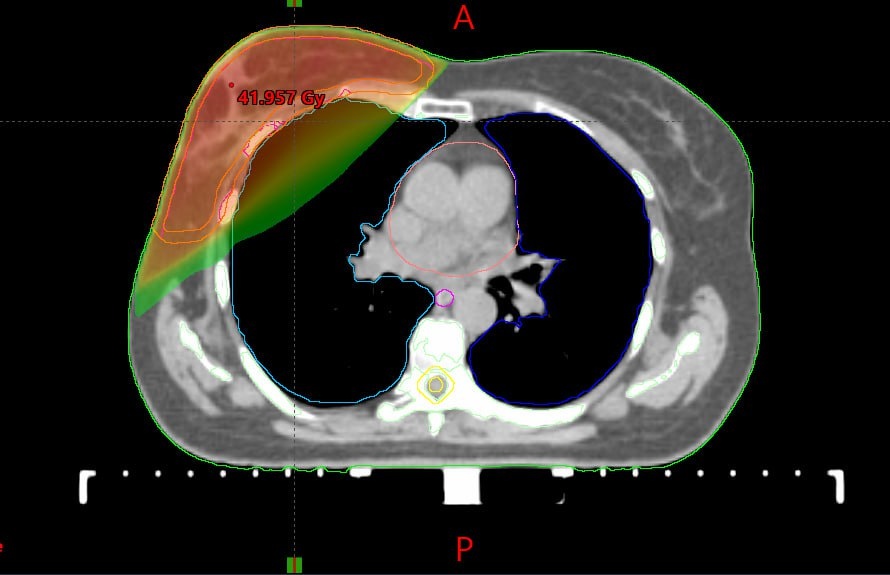

Курс длится около 3 недель (сеансы по 10-15 минут, 5 дней в неделю). Это похоже на рентген, только мощнее и точнее. Современные аппараты бьют прицельно по опухолевой зоне, максимально щадя сердце и легкие. 🎯